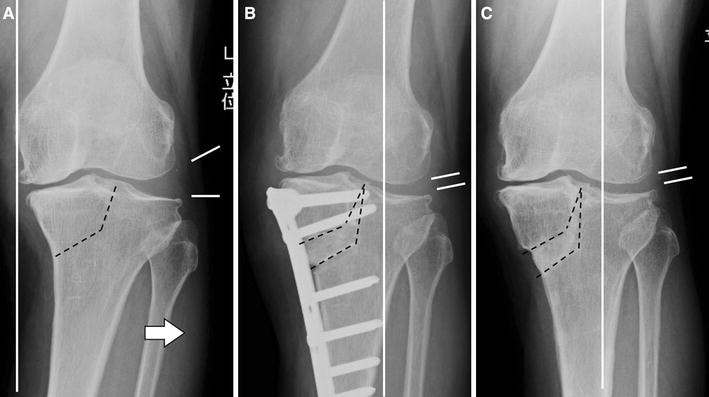

High Tibial Osteotomy (HTO)

Tibial Condylar Valgus Osteotomy (TCVO)